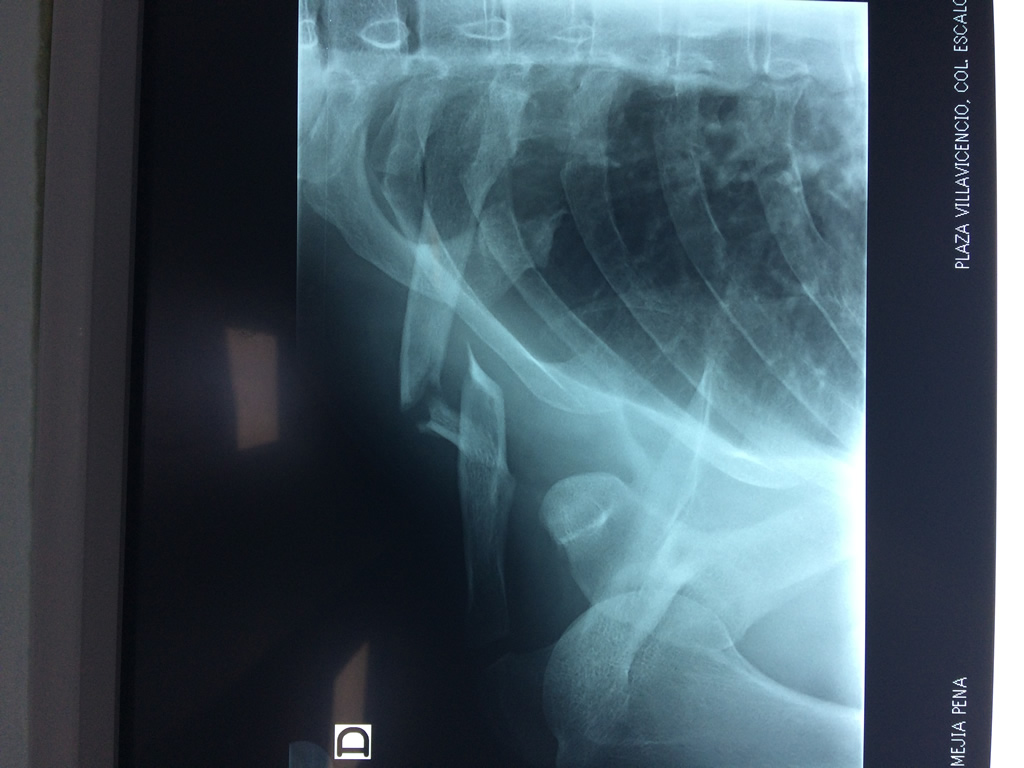

Húmero - Clavícula

La clavícula es un hueso largo, con forma de "S" itálica, situado en la parte anterosuperior del tórax. Junto con la escápula forman la cintura escapular. Se puede palpar por toda su longitud y se extiende del esternón al acromion de la escápula, siguiendo una dirección oblicua lateral y posterior.

Se considera el único medio de unión entre el miembro superior y el tórax. A pesar de su aspecto, similar al de un hueso largo, posee una estructura semejante a la de un hueso plano, ya que carece de epífisis y de diáfisis, lo que la harían entrar dentro de la clasificación de hueso largo. Carece de un canal medular propiamente dicho.